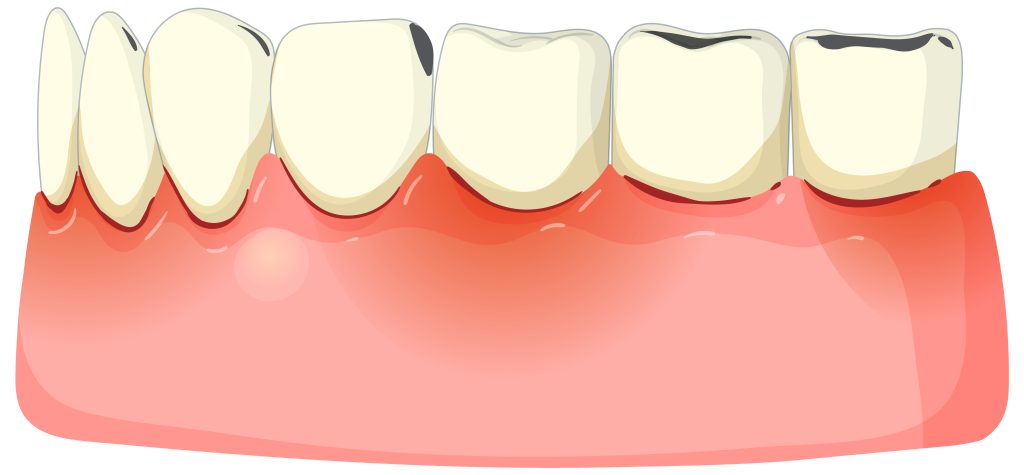

อาการเหงือกบวม เป็นสัญญาณเตือนว่าช่องปากของคุณกำลังเผชิญกับภาวะอักเสบ ซึ่งหลายคนมักปล่อยผ่านเพราะคิดว่าเป็นเรื่องเล็กน้อยหรืออาการจะหายไปเอง แต่แท้จริงแล้วเหงือกบวมอาจเป็นจุดเริ่มต้นของปัญหาช่องปากที่รุนแรงขึ้นได้หากไม่ได้รับการแก้ไขอย่างถูกวิธี ทำไมเหงือกถึงบวม? อาการเหงือกบวมเกิดได้จากหลายปัจจัย ตั้งแต่เรื่องใกล้ตัวไปจนถึงสภาวะทางร่างกาย 1. การสะสมของคราบจุลินทรีย์ สาเหตุอันดับหนึ่ง เมื่อแปรงฟันไม่สะอาด แบคทีเรียจะก่อตัวเป็นคราบเหนียวและเปลี่ยนสภาพเป็นหินปูน ซึ่งหินปูนนี้เองที่เป็นตัวกระตุ้นให้เหงือกเกิดการอักเสบ บวมแดง และมีเลือดออกง่าย 2. ปัญหาจากฟันคุด สำหรับช่วงอายุที่ฟันกรามซี่สุดท้ายกำลังขึ้น มักจะมีเหงือกปกคลุมอยู่บางส่วน ทำให้เศษอาหารเข้าไปติดและทำความสะอาดได้ยาก เกิดการอักเสบเป็นหนอง 3. การติดเชื้อจากฟันผุ หากฟันผุลึกไปถึงโพรงประสาทฟัน เชื้อโรคจะลามลงไปที่ปลายรากฟัน ทำให้เกิดเป็นฝีหรือถุงหนองที่เหงือกบริเวณนั้น 4. การเปลี่ยนแปลงของฮอร์โมน ในผู้หญิงช่วงตั้งครรภ์ หรือวัยรุ่น อาจพบอาการเหงือกบวมง่ายขึ้น เนื่องจากฮอร์โมนที่เปลี่ยนแปลงส่งผลต่อการตอบสนองของเหงือกต่อคราบจุลินทรีย์ 5. ปัจจัยด้านสุขภาพอื่นๆ ไม่ว่าจะเป็น การขาดวิตามินซี, ผลข้างเคียงจากยาบางชนิด (ยาลดความดันหรือยากันชัก) หรือโรคประจำตัวอย่างเบาหวานที่ทำให้ร่างกายมีภูมิคุ้มกันต่ำและติดเชื้อในช่องปากได้ง่าย สัญญาณอันตรายที่ต้องรีบพบทันตแพทย์ ไม่ใช่ทุกกรณีที่การบวมจะหายเองได้ ควรสังเกตอาการอย่างละเอียด วิธีดูแลและบรรเทาอาการเหงือกบวมเบื้องต้น หากอาการบวมยังไม่รุนแรง คุณสามารถปรับเปลี่ยนกิจวัตรเพื่อช่วยให้อาการเหล่านั้นดีขึ้นได้ โดยวิธีต่อไปนี้ 1. แปรงฟันให้ถูกวิธี ใช้แปรงสีฟันขนอ่อนนุ่ม แปรงให้ทั่วรวมถึงบริเวณรอยต่อเหงือก แต่ต้องแปรงอย่างเบามือเพื่อไม่ให้เหงือกบาดเจ็บเพิ่ม 2. ใช้ไหมขัดฟันทุกวัน ช่วยกำจัดเศษอาหารในซอกฟันที่แปรงสีฟันเข้าไม่ถึง ซึ่งเป็นแหล่งสะสมของเชื้อโรค […]